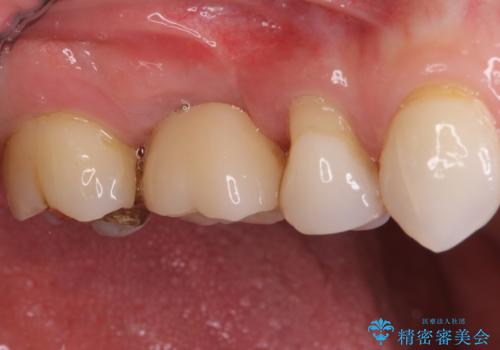

機能性と清掃性、更には審美性も考慮し、土台となるアバットメントにはジルコニアカスタムアバットメントを採用しました。

ジルコニアカスタムアバットメントは、歯肉ラインに金属が見えにくいというだけでなく、クラウンを装着する土台の形が天然歯と近い形態となるため、清掃性が高く歯肉が腫れにくいというメリットがあります。